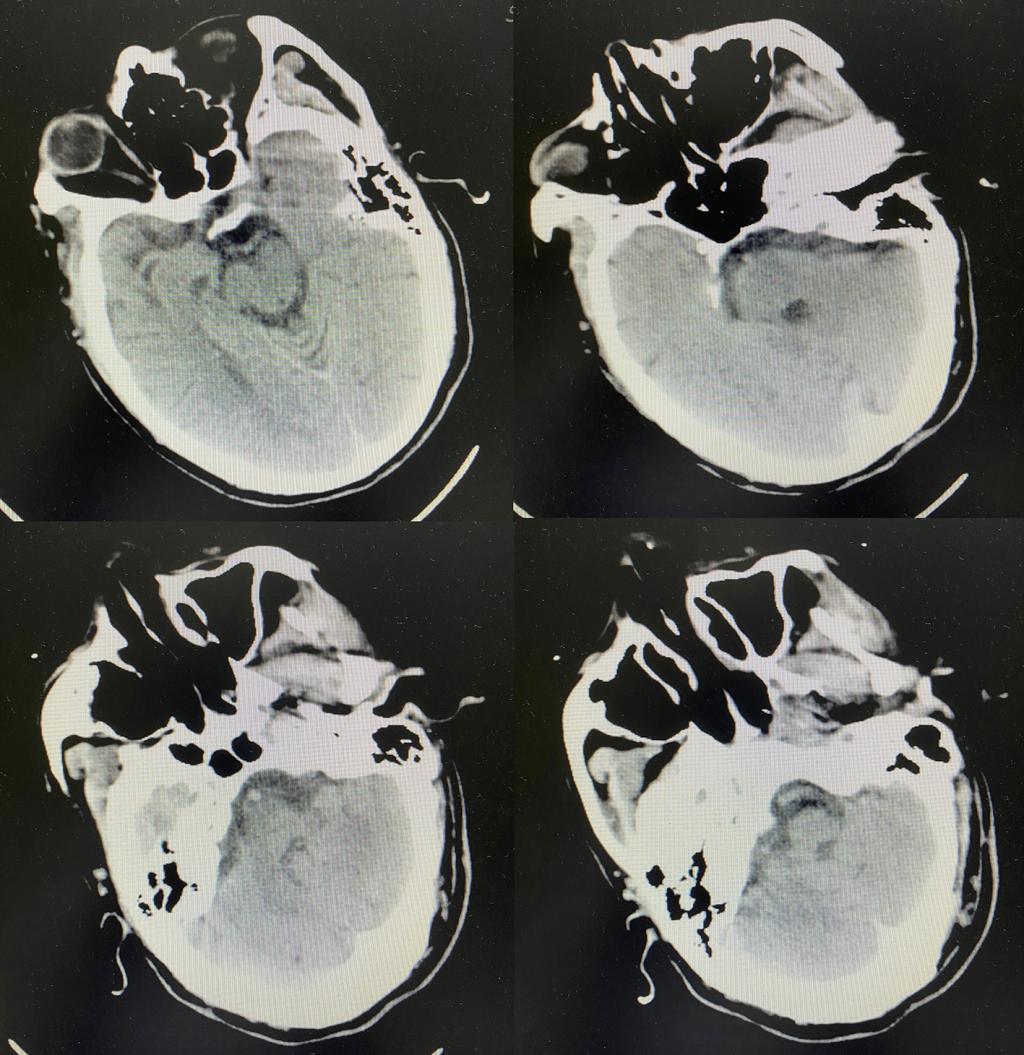

颅脑CT未见出血

术后复查颅脑CT无脑出血转化